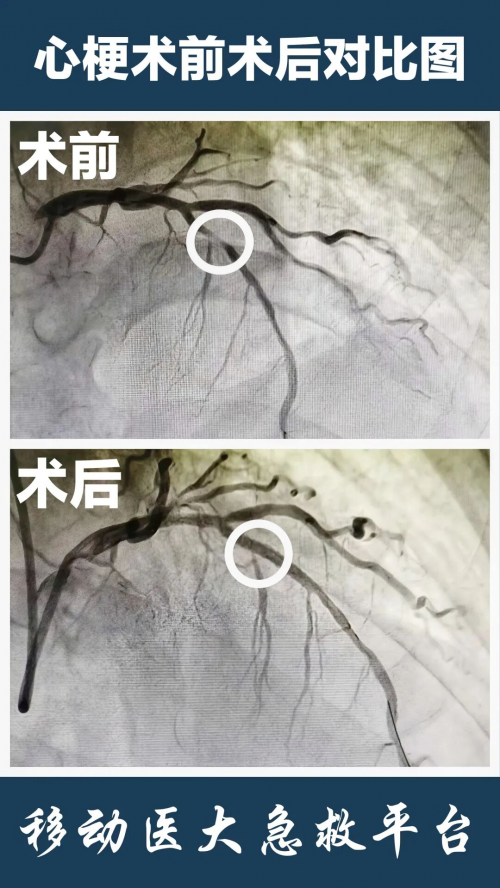

明确诊断后立即启动MDT,急诊心内介入手术团队就位,迅速对患者病情进行评估,判定其具备急诊介入手术指征。在与家属充分沟通病情及治疗方案、获得家属同意后,将患者送入导管室行急诊PCI手术,冠脉造影显示左冠状动脉前降支严重狭窄,立即行前降支球囊扩张、支架置入术,造影显示狭窄解除、血流恢复。术后患者腹痛消失,生命体征平稳。